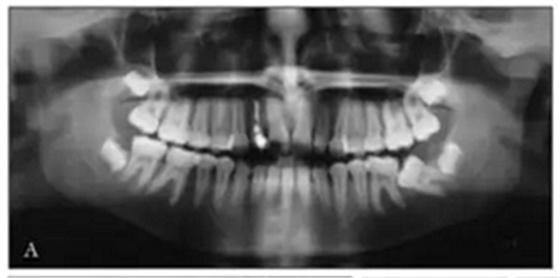

全景X線(圖3)顯示所有牙齒均存在,包括第三磨牙的牙胚。左下頜第二磨牙近中阻生。X線片顯示以前根管治療的上頜右側(cè)切牙(據(jù)報(bào)道有窩溝內(nèi)陷),對側(cè)切牙有根尖周圍病變以及窩溝內(nèi)陷的典型影像學(xué)表現(xiàn)。上頜中切牙的根部顯示先前存在的吸收。頭影測量分析顯示上頜骨和下頜骨矢狀和垂直關(guān)系正常。上頜和下頜門牙過度唇側(cè)傾斜。